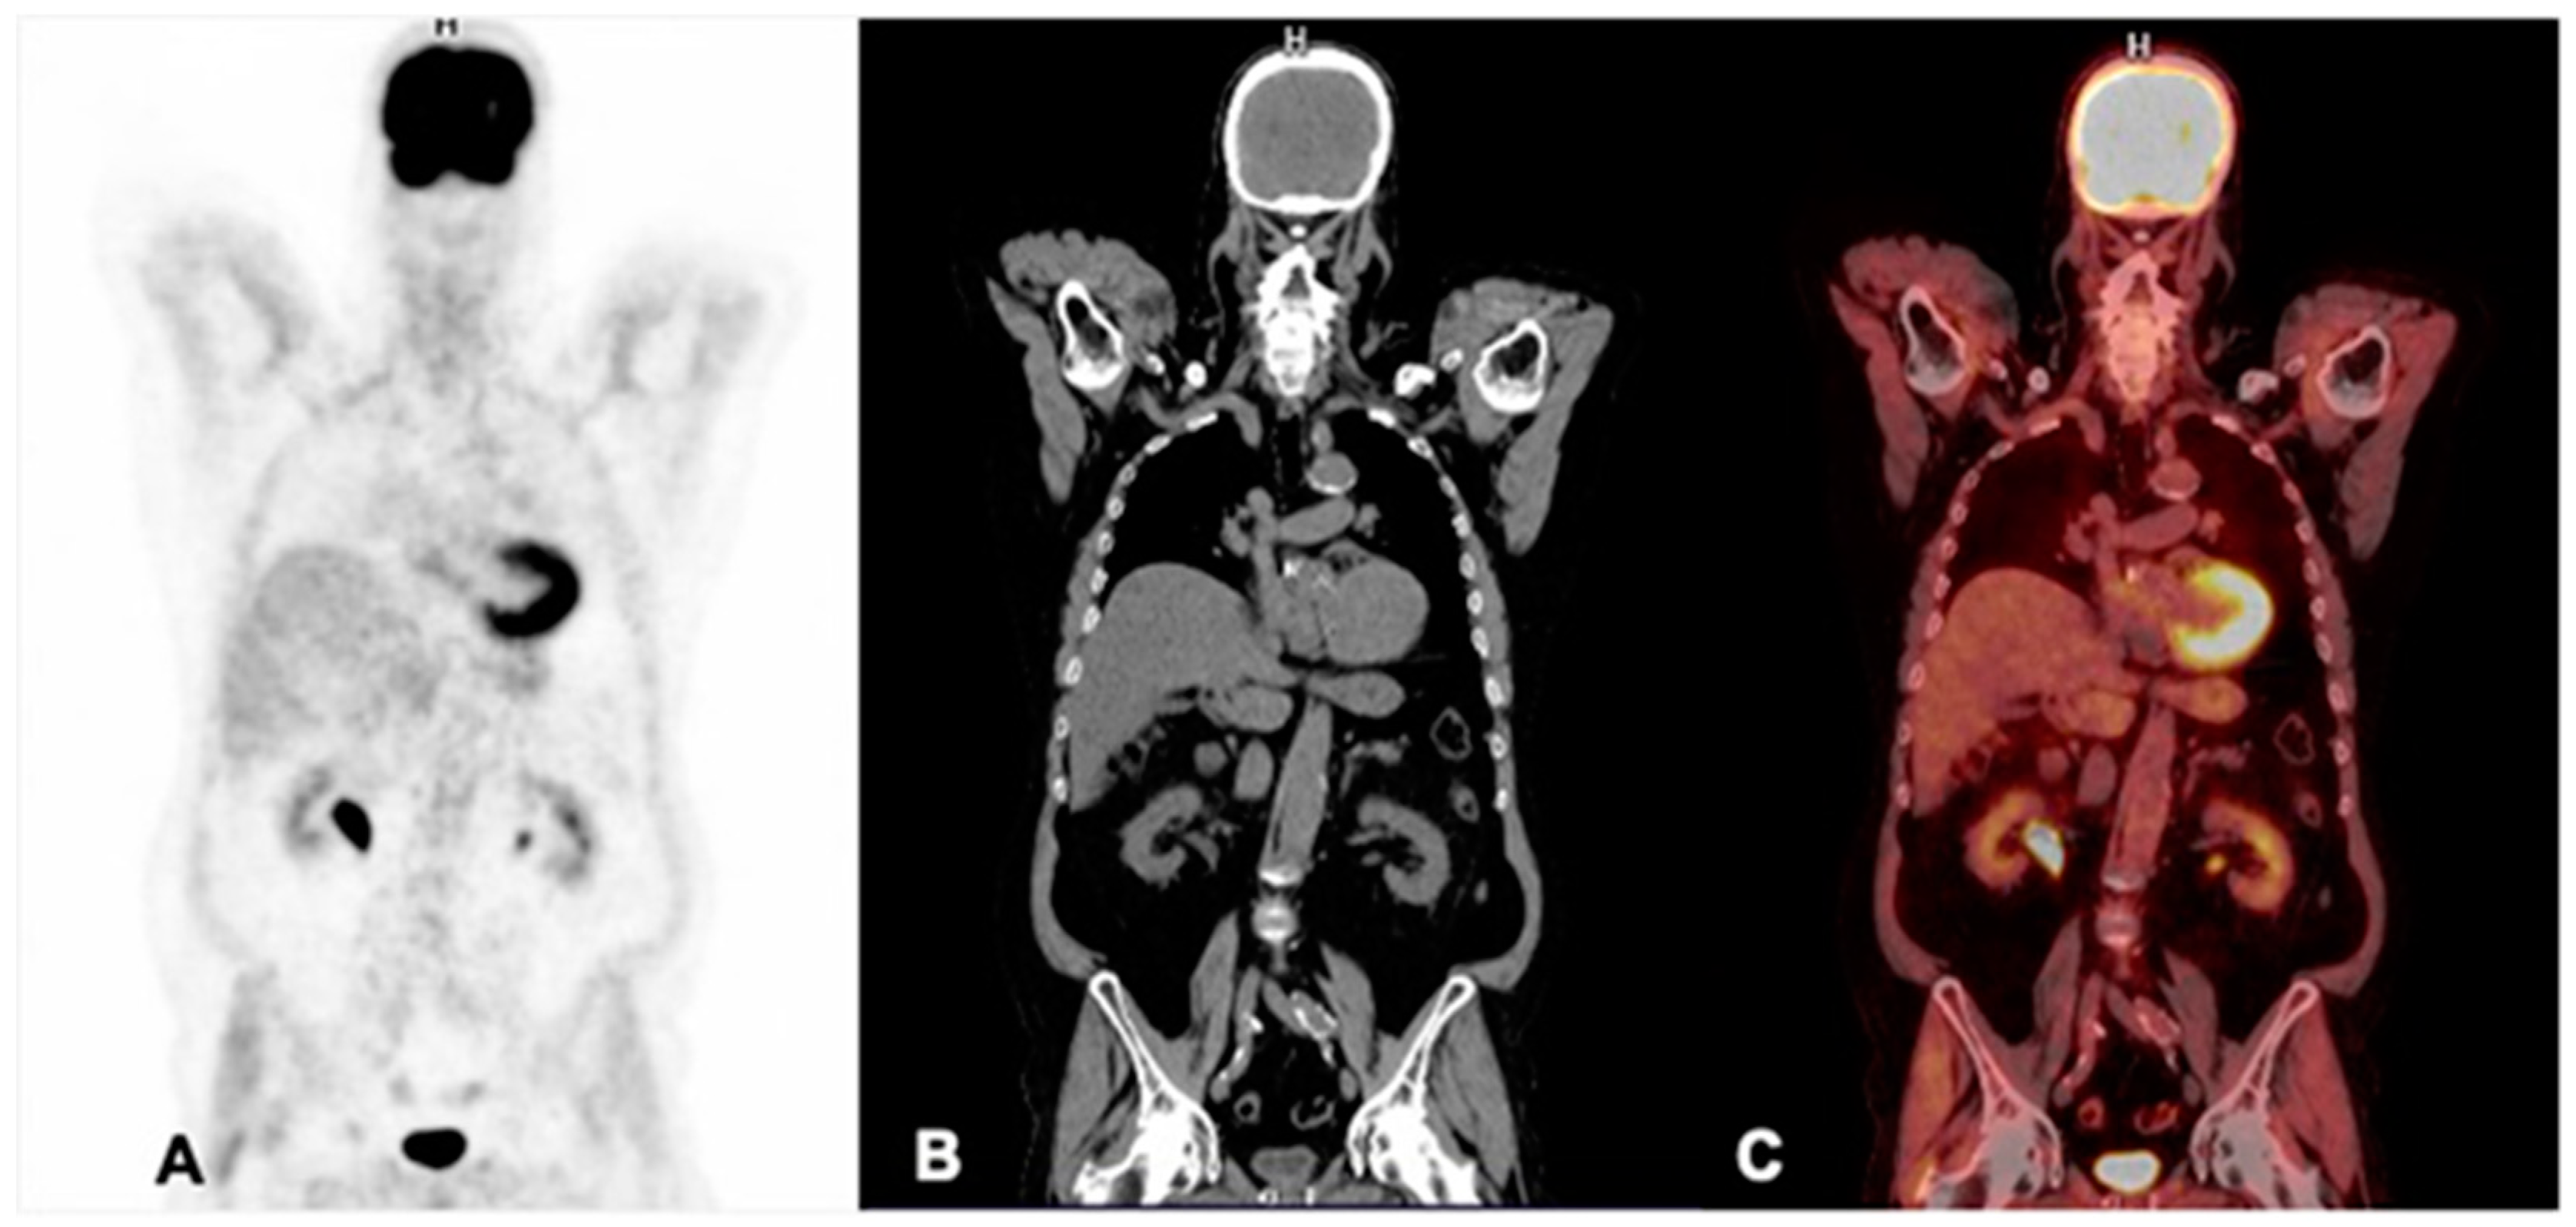

7.1. 177Lu-PSMA

7.2. 225Ac-PSMA